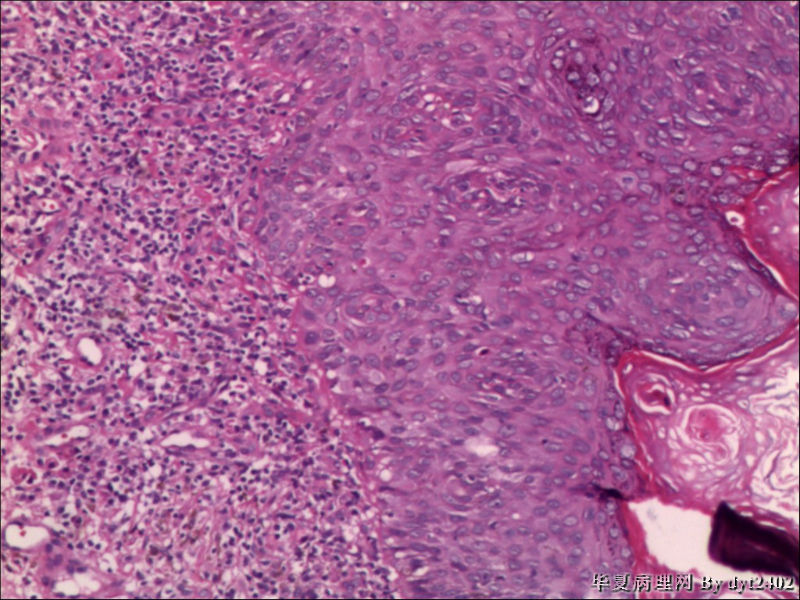

这样的外阴病变 发个原位癌是否合适?

• 这样的外阴病变 发个原位癌是否合适?图1

图1

原位癌够了,不排除其他地方有浸润。

似乎有浸润了

VIN III,做个银染或者标个免疫组化看一下基底膜是否完整。

看上去好像还完整 只是经常看见图5 那样结构的就觉得可能还有更重病变

VIN III